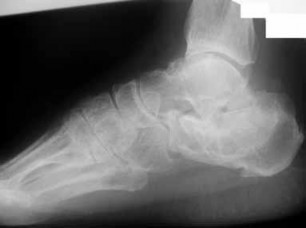

Question 28

Which of the following is true of calcaneal fractures? fragments on sagittal CT scan. fixation.

Explanation:

Bilateral fractures occur in 5–10% of cases. Calcaneal fractures occur after an axial load and are bilateral in 5–10% of cases. They are associated with a spinal injury in about 10%. The majority (75%) are intra-articular, and result in a decreased Bohler’s angle (line drawn by connecting the anterior process, highest point on posterior articular surface and superior tuberosity on the lateral radiograph). The Sanders classification is based upon the number and location of articular fragments on the coronal CT scan, with four types, based on the number of fragments of the posterior facet, with displacement of 2 mm considered significant. The wound complication rate is reported to be up to 30%.